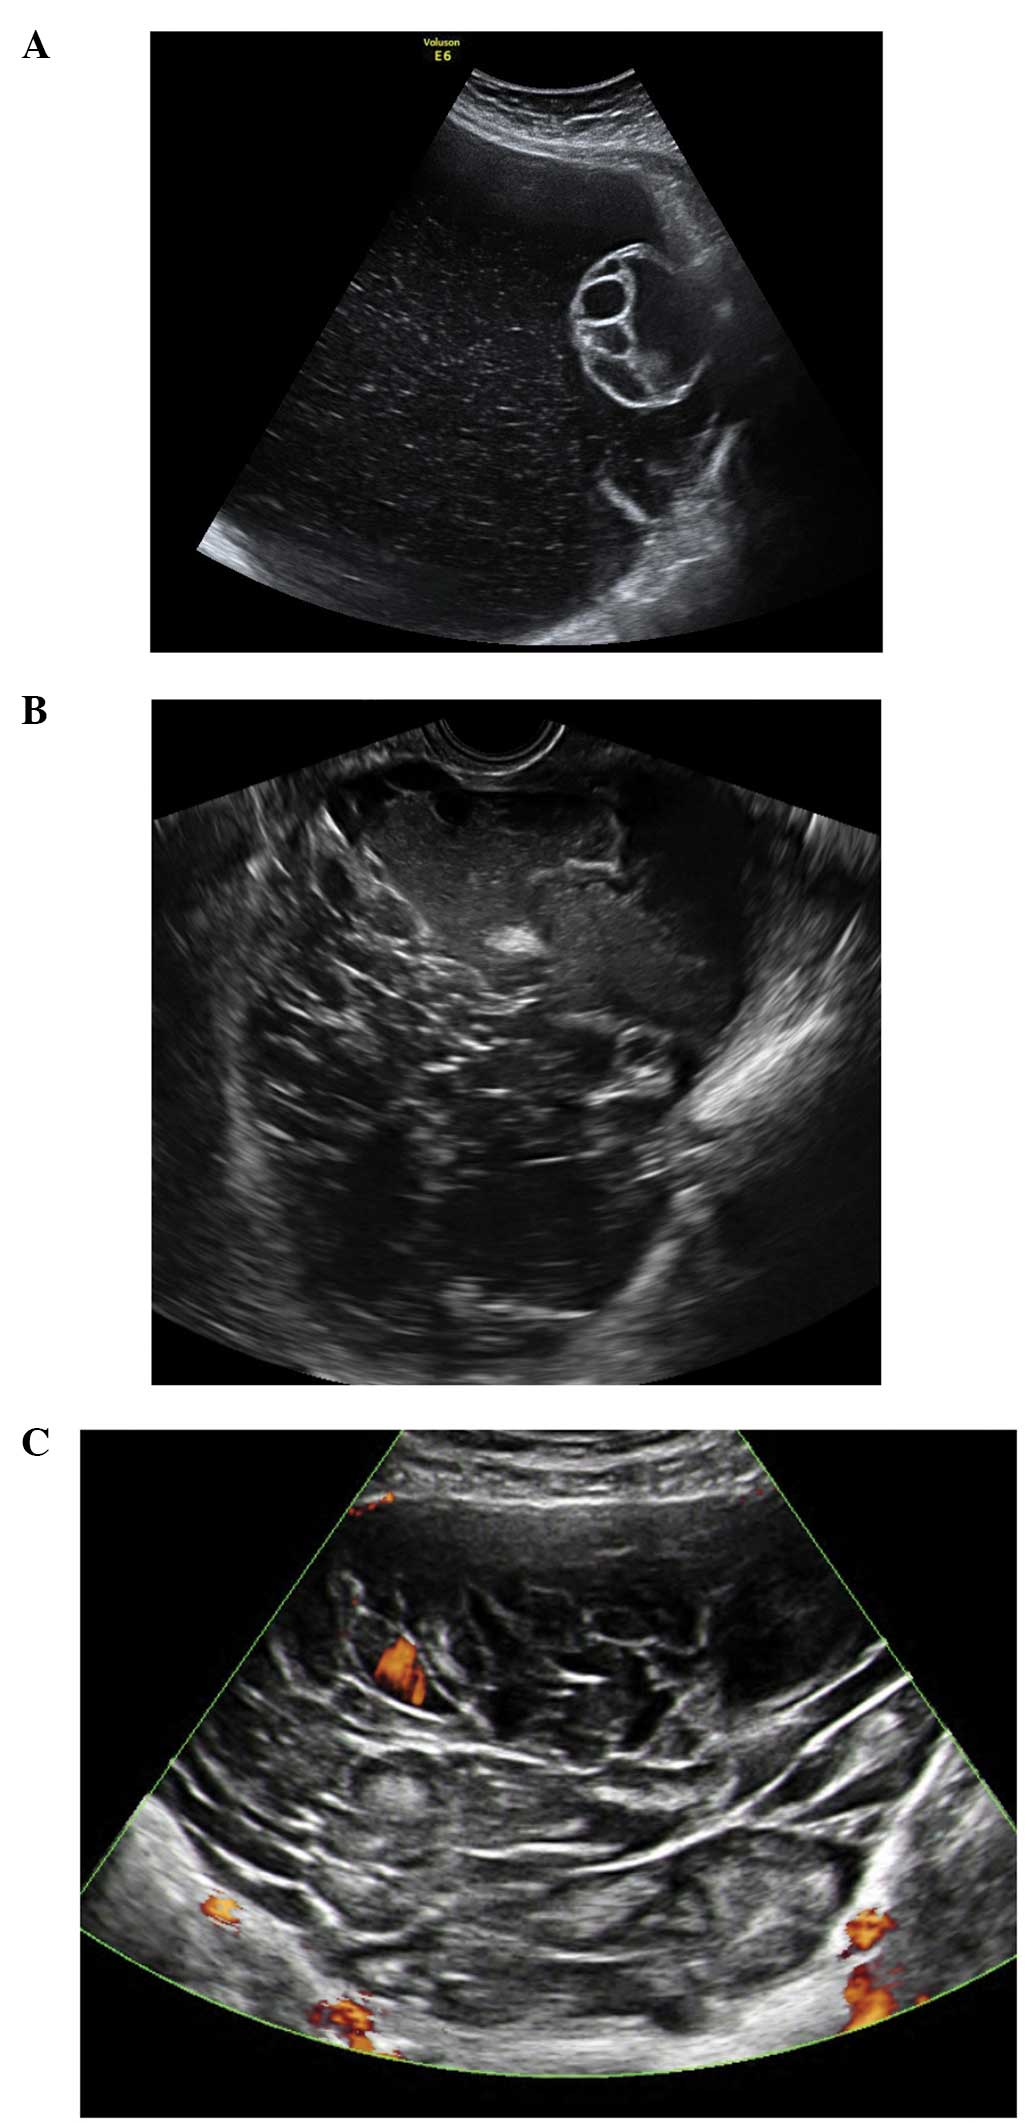

Primary invasive ovarian epithelial cancer

Stage 1 primary invasive ovarian epithelial cancers share similar ultrasound characteristics to borderline tumors, but they differ significantly from the appearances of later stage disease (44) (Fig. 22). They often contain papillary projections and less commonly are purely solid (44).

Figure 22

Primary invasive ovarian epithelial cancers. (A) Stage 1 clear cell carcinoma of the ovary. (B) Unilocular solid early invasive cancer with increased vascularity on color Doppler.

Later stage primary ovarian tumors are usually multilocular with a high proportion of solid tissue and are frequently associated with ascites as well as metastatic disease to the peritoneum, omentum and elsewhere in the abdomen and pelvis (44). They are also significantly vascular with high color scores (3–4) (44) (Fig. 23).

Figure 23

Advanced primary ovarian cancers. (A) Multilocular solid ovarian serous adenocarcinoma with increased vascularity. (B) Peritoneal deposits from late stage primary ovarian cancer in in the pouch of Douglas with ascites.